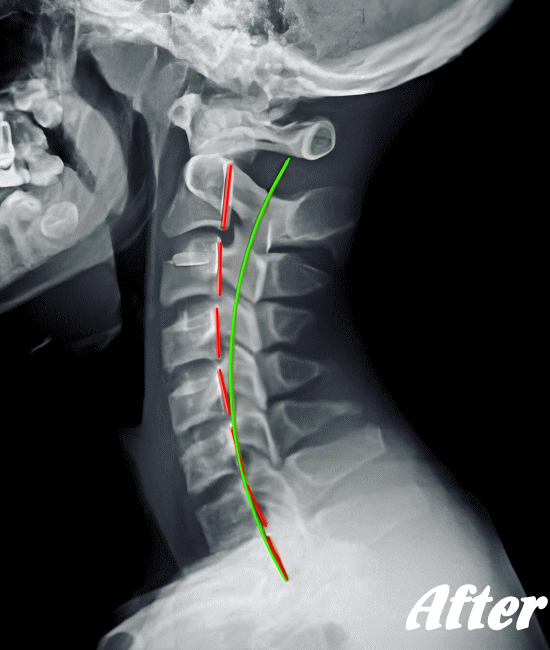

レントゲン撮影やCT、MRIなどにより診断します。頚椎症と診断されると、主に以下の治療が行われます。基本的には、保存療法がおこなわれます。

HALOカイロプラクティック☆平和島整体院では、骨盤から背骨全体(腰椎、胸椎、頸椎)を調整し、肩甲骨の動きを柔軟にし、首周りの筋肉をゆるめ、頚椎の骨と骨との間隔を広げ、動きを滑らかにして、首の負担を軽減させながらバランスを整える施術を行います。

頚椎症は、速効矯正・即効施術の【体の整体】の適応になります。